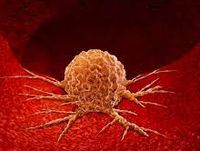

眼の疾患  腫瘍

腫瘍  腫瘍

腫瘍  腫瘍

腫瘍  腫瘍

腫瘍  腫瘍